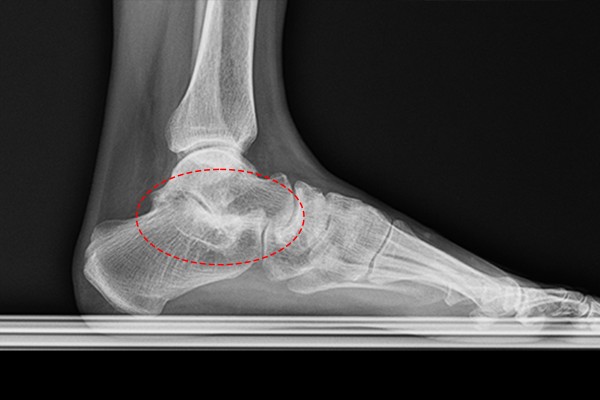

환자분의 발, 발목 상태를 파악하기 위해 X-RAY 검사를 시행하였습니다. 먼저 정상적인 우측발은 거골과 종골 사이 공간이 확인되는 반면,

정상적인 우측 발에 비해 통증이 있는 좌측 발목은 거골하관절이 관절염이 온 것 처럼 좁아진 소견이 보였고, 정밀한 확인을 위해 CT검사를 추가로 시행하였습니다.